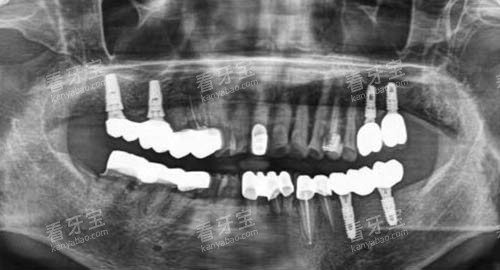

在种植牙手术前,医生们会对患者进行齐全的口腔检查,包括口腔X光片、CT扫描等,以较准了解患者的口腔状况,如牙槽骨的密度、高度、宽度等。

根据患者的具体情况,医生会制定个性化的种植方案。

例如,对于牙槽骨条件较差的患者,医生会采用骨增量技术,增加牙槽骨的量,为种植牙提供更好的基础。

智能化种植技术利用计算机辅助设计和制造技术,能够正确地模拟种植体的植入位置和角度,提高种植的较准性和可行性。

在智能化种植过程中,医生会通过口腔扫描获取患者口腔的三维数据,然后利用特色的软件进行种植方案的设计。

在手术中,医生可以根据智能化导板的引导,较准地将种植体植入到预定的位置,大大提高了手术的精度和安心性。